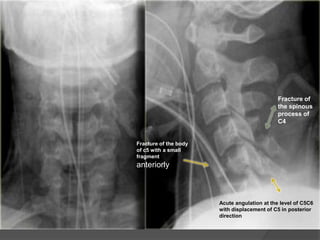

Fracture of

the spinous

process of

C4

Fracture of the body

of c5 with a small

fragment

anteriorly

Acute angulation at the level of C5C6

with displacement of C5 in posterior

direction